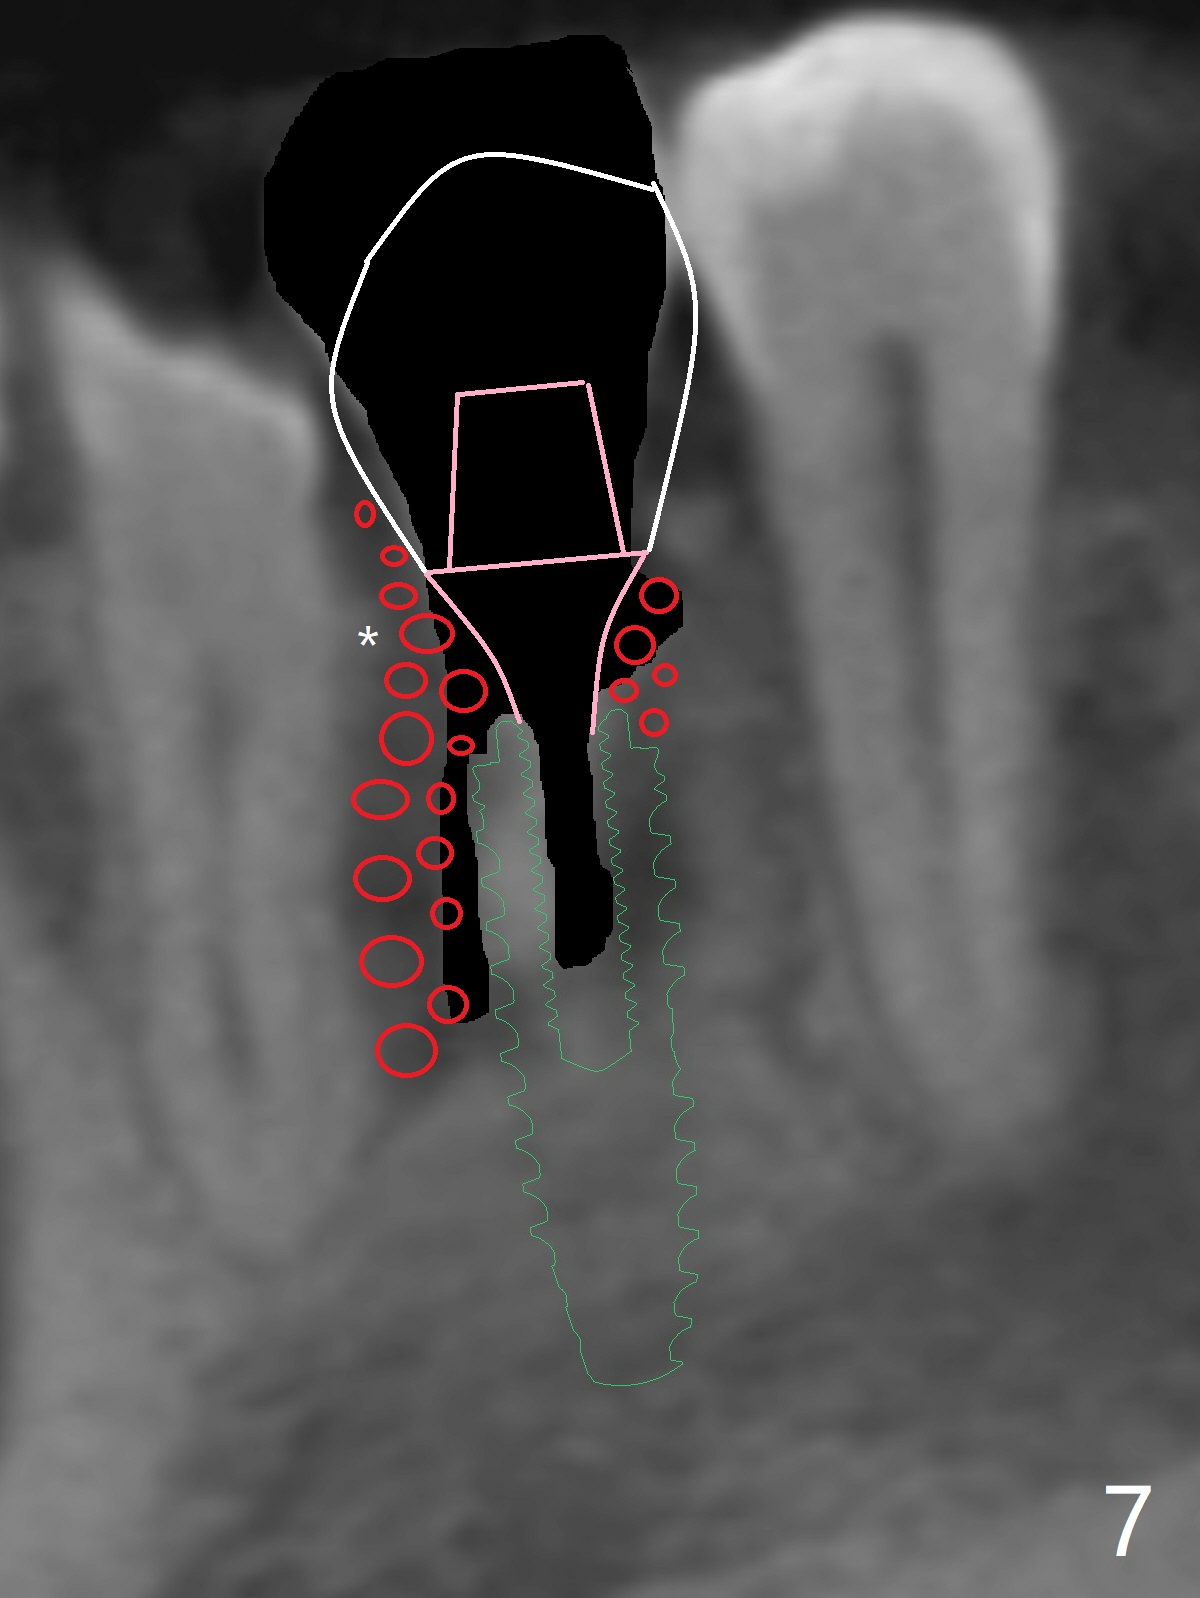

A -year-old man seeks treatment for the tooth #28 with severe bone loss (Fig.1 islands of bone remaining in the mesial surface of the tooth #27, reossification center for grafted bone). The tooth #28 has oblique root fracture (Fig.2 lingual view). One of treatment options is to place an immediate implant (green) at #28 as lingual as possible (Fig.3,4 (coronal section, after extraction (black area))). Sticky bone is placed buccal (Fig.5 red); some of bone graft will be pressed into the space between implant threads (arrowheads, bone and implant contact area expectedly to be higher than delayed placement due to less pressure to the native bone). In spite of severe bone loss between #27 and 28 (Fig.6 (sagittal section) after extraction), the crestal bone appears to exist in the mesial surface of #27 (*). With placement of an abutment (Fig.7 pink) and an immediate provisional (white), bone graft is packed as high as supracrestal (red). Restoration of the crest is expected to be better than socket preservation.